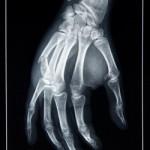

Radiografie

Da, stiu, nu am fost foarte cuminte :( Morala: Nu e bine sa bati cu pumnul in masa! PS: Multumesc, Alina, pentru tot :*